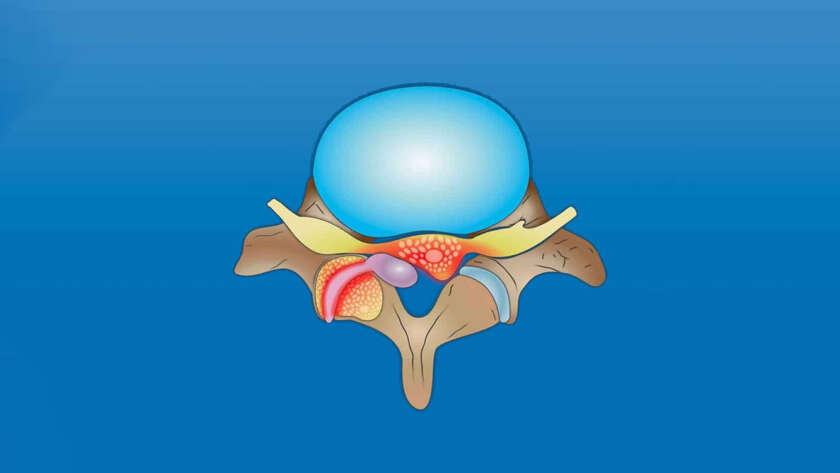

A corrida não é necessariamente proibida em todos os pacientes acometidos com a hérnia de disco, mas precisa ser avaliada de forma individualizada. Em algumas situações, ela pode ser bem tolerada; em outras, pode piorar os sintomas e aumentar a sobrecarga na coluna.

Como a Corrida Impacta a…